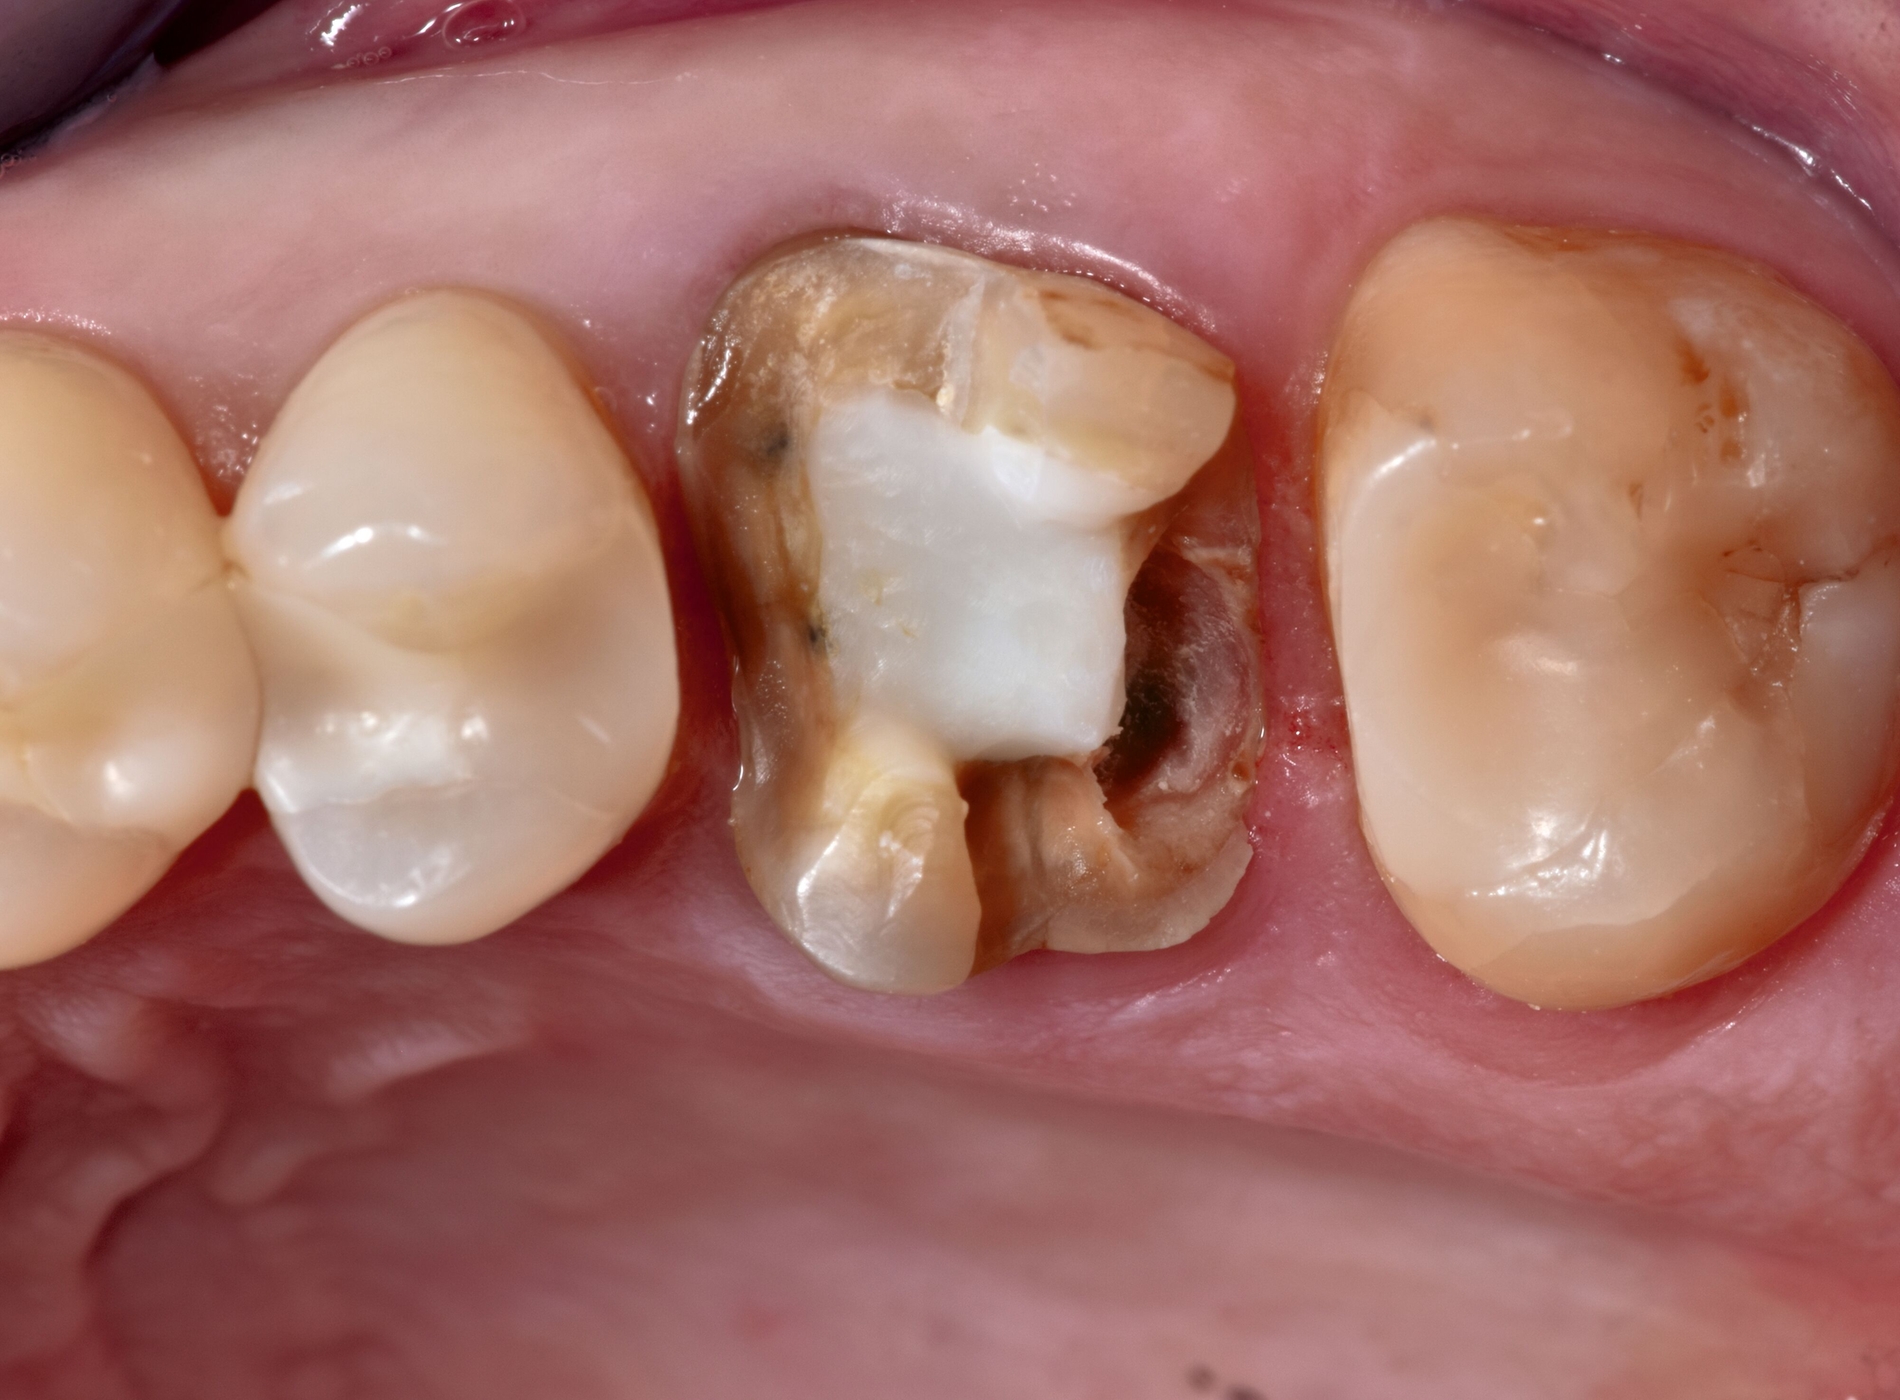

Zur definitiven Versorgung des subgingivalen Defekts im distalen Bereich des Zahnes 26 wird der Patientin eine Kastenelevation mit Komposit und anschließend eine restaurative Versorgung mit einer CAD/CAM-gefertigten Teilkrone aus Lithium-Disilikat-Glaskeramik vorgeschlagen.

Im weiteren Restaurationsverlauf erfolgen zunächst eine Nachpräparation und das Finieren des Zahnes 26, anschließend die optische Abformung für die Herstellung einer Teilkrone aus Lithium-Disilikat-Glaskeramik (siehe Materialliste). Nach Anprobe der indirekten CAD/CAM-Restauration wird die Restauration gereinigt und für 20 s mit Flusssäure angeätzt, mit einem speziellen MDP-haltigen Primer bestrichen und in einem Lichtschutzgefäß gelagert. Nach Trockenlegung und Reinigung wird der Zahn 26 angeätzt, ein Adhäsiv aufgetragen, die Deckrestauration mit Befestigungskomposit bestrichen und adhäsiv befestigt (Abbildung 3, Materialliste).